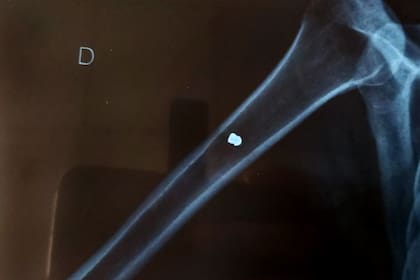

El balín llegó hasta el hueso y el hombre deberá ser operado

Pasadas las 19, la esposa del hombre agredido, contó a LA NACION: "Fuimos al Cemic a la guardia de traumatología. Pensábamos que le sacaban el balín, lo limpiaban, vendaban y nos íbamos a casa, pero no. El balín llegó al hueso. Le tienen que hacer una cirugía, en principio, será el lunes".